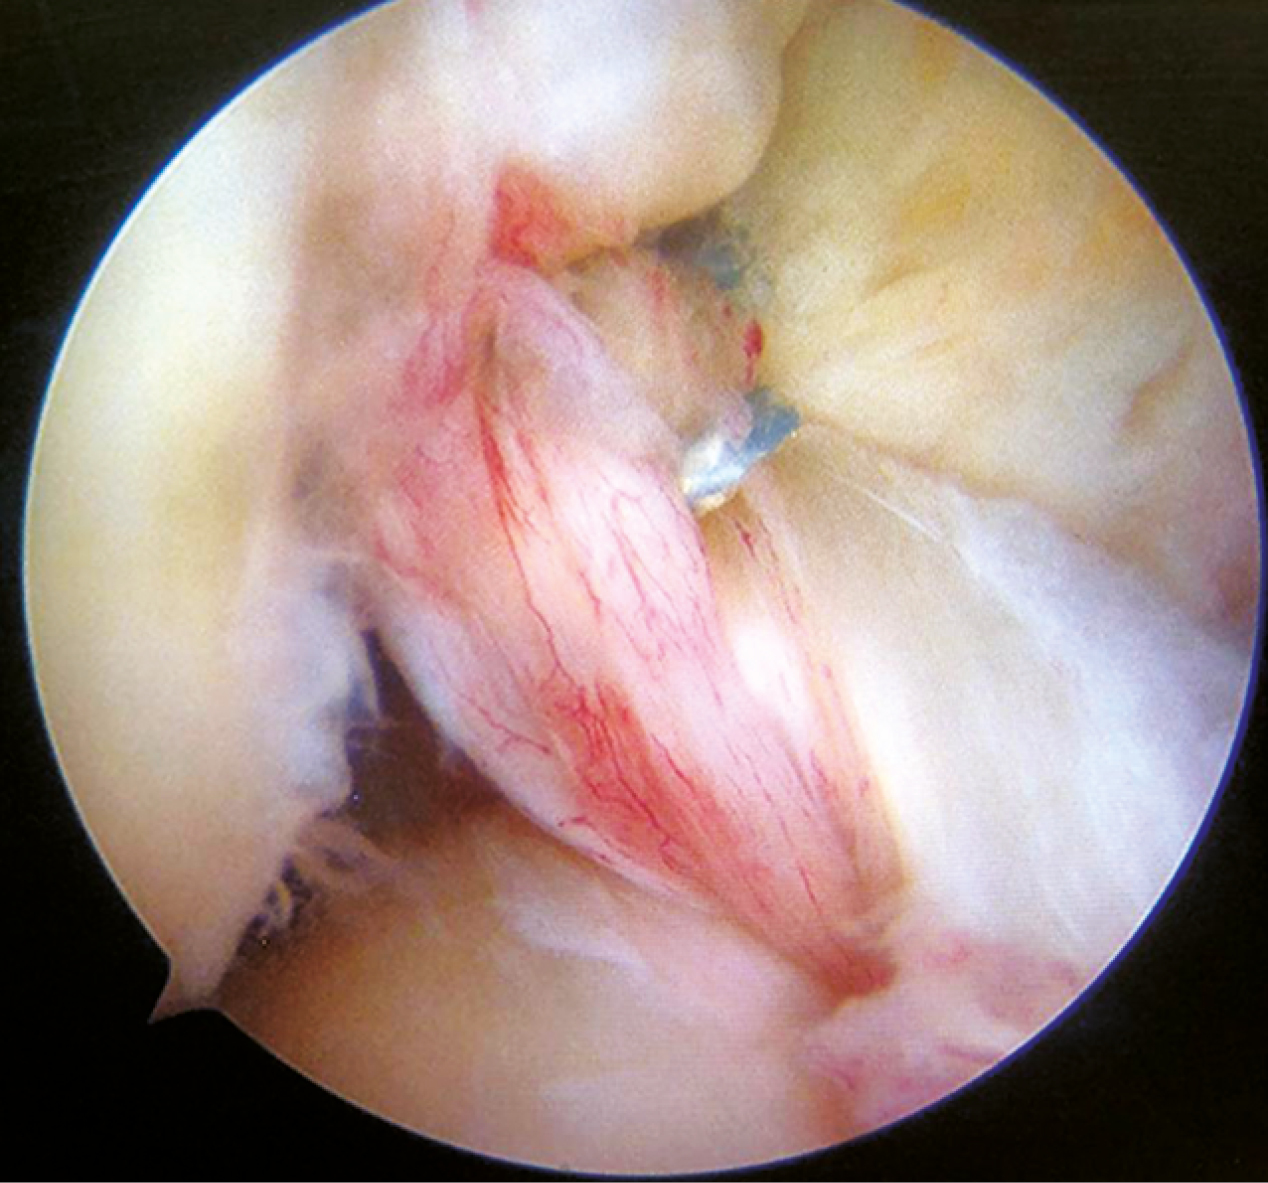

Clinical evaluation of anterior knee instability before surgery was performed using Lachman and anterior drawer tests. Magnetic resonance imaging (MRI) with a magnetic field strength of at least 1.5 was utilized for visualizing intra-articular knee structures. The final decision on the feasibility of either surgical method was made intraoperatively following arthroscopic examination of the ACL and confirmation of the injury type’s adherence to the study’s inclusion criteria (Figure 3).

Figure 3. Arthroscopic image of the ACL injury of type A (Gächter classification)